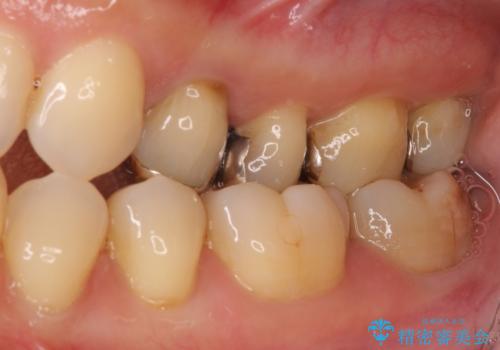

- 神経が取り除かれた歯が欠けてしまったとのことで来院された患者様です。

破折線が歯肉の中、深いところにまで及んでいる場合には歯周外科の適用となることを伝えた上で、補綴治療を行うこととしました。

破折部位を除去したところ、外科処置が必要な深さまで破折線が及んでいなかったため、速やかにジルコニアクラウンにて補綴を行うことになりました。

神経が取り除かれた歯、特に奥歯では、歯の破折が起こりやすいので、クラウンによる補綴治療が必要であることを実感した治療でした。